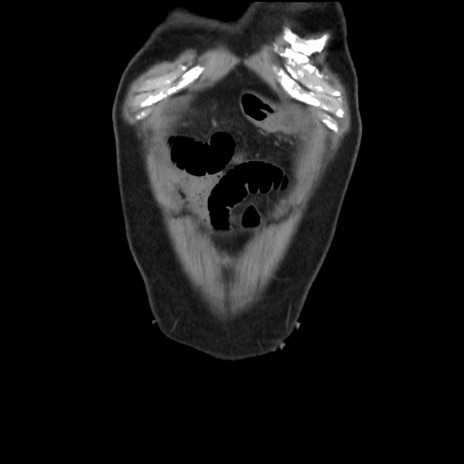

横断像